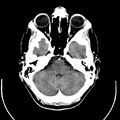

تصوير مقطعي حاسوبي

التصوير المَقْطَعي الحاسوبيX-ray computed tomography نظام تصوير بالأشعة السينية، يُسْتخدم لتصوير مختلف أجزاء الجسم مثل الرأس والقلب والبطن. ويستعين الأطباء بالتصوير المقطعي الحاسوبي على تشخيص الأمراض وعلاجها. وتسمى هذه التقنية أيضًا التصوير المقطعي المحوسب أو التصوير المقطعي المحوري المحوسب.

ويستعمل الأطباء فحوص التصوير المقطعي الحاسوبي لتشخيص كثير من الحالات مثل الأورام والإصابات وتجلطات الدم وكسور العظام. ويساعد التصوير المقطعي الحاسوبي أيضًا في معالجة بعض الأمراض، التي قد تتطلب جراحة بطريقة أخرى. فمثلا،ً يمكن للأطباء استعمال التصوير المقطعي الحاسوبي لإرشادهم إلى إدخال القثطار (أنبوب رفيع) إلى خُرّآج في الجسم لسحب الصديد من المنطقة الملوثّة.

معرض الصور